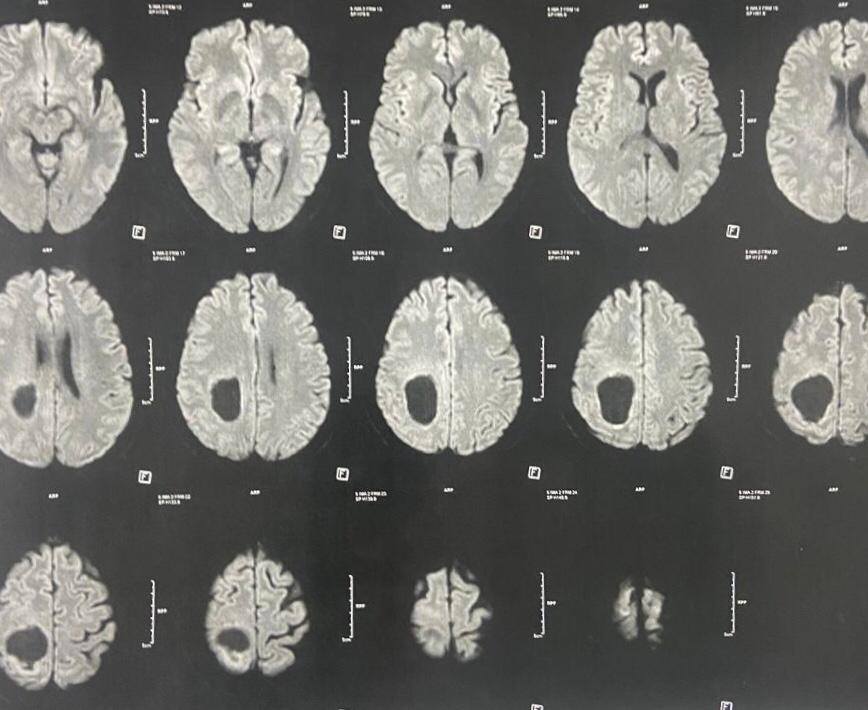

ومن جانبه، أوضح الدكتور مجدي القاضي، عميد كلية الطب البشري ورئيس مجلس ادارة المستشفيات الجامعية، أن المريض كان يعاني من اضطراب بدرجة الوعي وشلل نصفي بالجانب الأيسر، وتبين من الفحوصات وجود ورم بالمخ بحجم ٧×٥×٤ سم، وقد تم استئصاله بالكامل خلال جراحة استغرقت ٤ ساعات، مشيرًا إلى أن الفريق الجراحي استخدم تقنية حديثة تعتمد على حقن الصبغات الورمية لتحديد حدود الورم بدقة.

وأشار الدكتور أحمد كمال عبدالحميد، المدير التنفيذي للمستشفيات الجامعية واستاذ جراحة المخ والأعصاب والعمود الفقري، والذي أجرى الجراحة، إلى أن العملية تمت بإستخدام ميكروسكوب جراحي متطور، والحفار الكهربائي لفتح عظام الجمجمة، مما ساهم في الوصول الآمن إلى الورم واستئصاله بالكامل دون التأثير على الأنسجة الحيوية. مضيفًا أن المريض استعاد وعيه بالكامل بعد الجراحة، وعادت حركة الأطراف إلى طبيعتها.